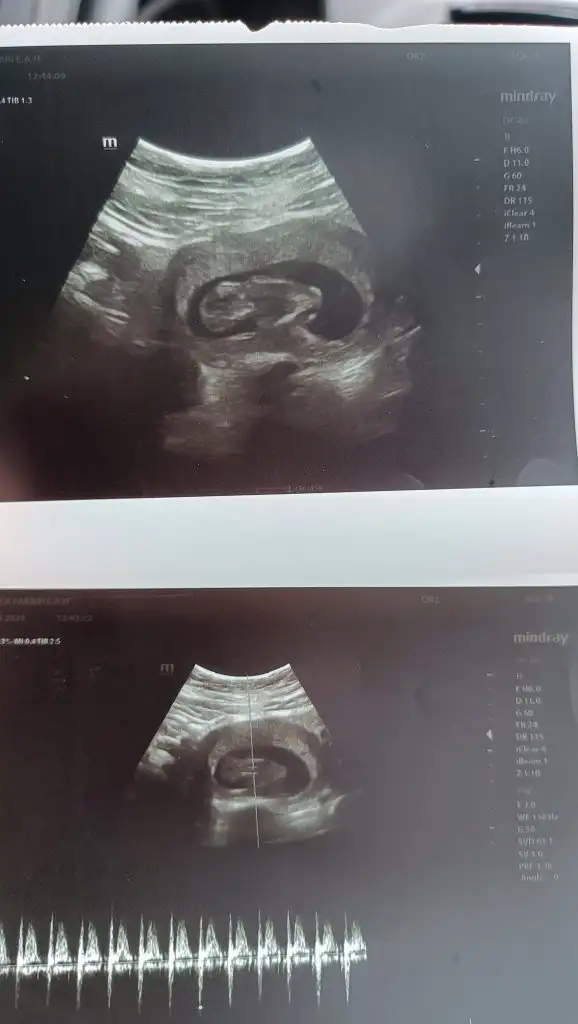

5 ve 14. haftaya kadar olan ultrason fotolarınızı paylaşın. Vajinadan mı yoksa karından mı çekildiğini ve kaç haftalık olduğunu da mutlaka belirtin.

Merhaba benim içinde bakarmisiniz karından ultrasonSelam Kızlarbir çok kişi gruplardan beni bilir. Yine yetiştim imdatlara